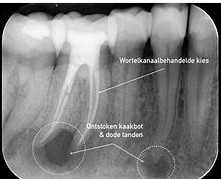

Onder fotos van het internet geplukt over een wortelpunt kaakbot peripicaal ontstekingen |

- Ik zie nu op de fotos boven alleen het tandvlees abces .

- Abes links onder , op de foto 37m diep caries tot zenuw en 36d ook (de elementen) Hij heeft geoordeeld op naar aanleiding van de e foto die hij op 07-10-2021 tot beschikking had en was doorgestuurd door een andere praktijk STASSEN&STASSEN gemaakt op 24-24-02-2021 +/- 9 maanden later (zie onder foto 1) en die praktijk ziet maar 1 wortelkanaal behandeling op eerste de foto onder op element 36 , en op 37 een gaatje was maar een vlekje (zie pagina begroting)

- De ontsteking is zichtbaar op de fotos . Ik zie op de foto wel een tandvlees ontsteking bij element 36 de tand die weggefreest is .

- Element 37 die een onnodige wortelkanaal behandeling heeft gehad zie ik geen wortelpunt ontsteking .